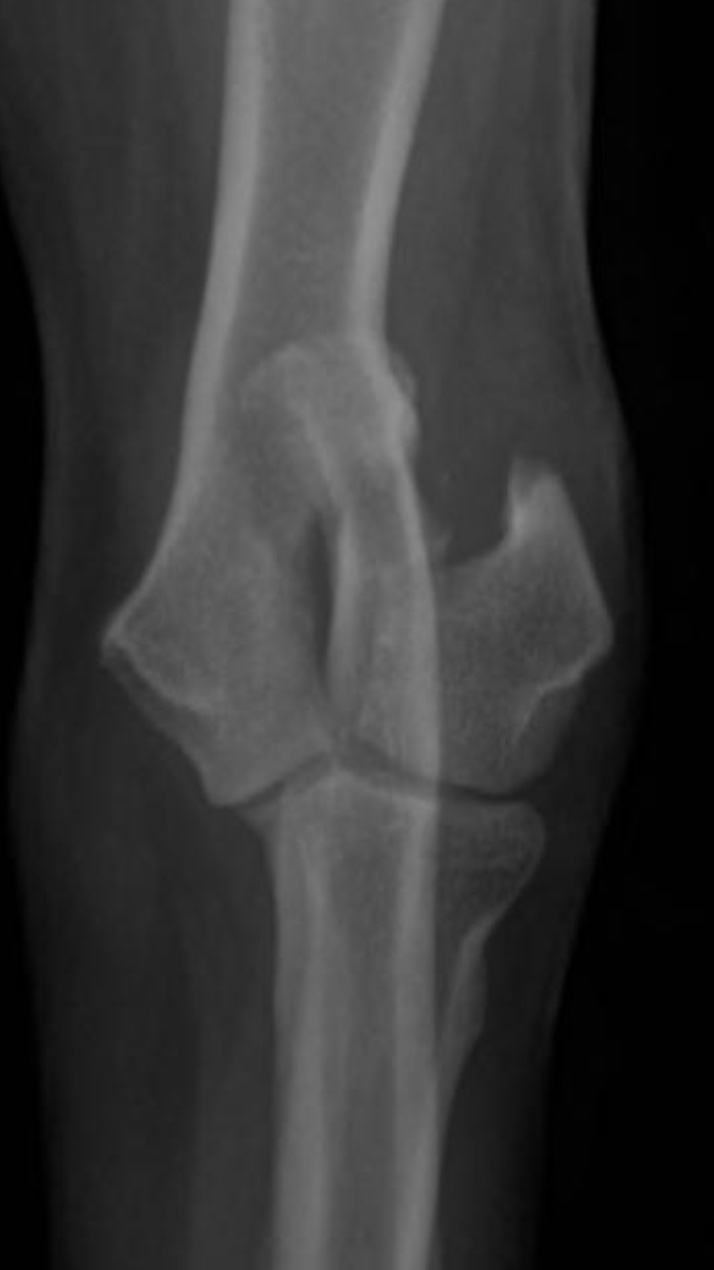

Humeral condylar fractures are one of the most common fore limb injuries in dogs. Prompt surgical repair is essential for the best long-term outcomes.

Humeral condylar fractures are breaks at the lower end of the humerus (upper fore limb bone) where it forms part of the elbow joint. This area has two rounded surfaces, or condyles — the medial and lateral — and the fracture can involve just one side (unicondylar) or split through both (bicondylar).

These injuries are relatively common in certain breeds and can occur even from low-impact events like falling or jumping down from furniture. Young dogs and breeds such as French Bulldogs are overrepresented. Spaniel breeds may also be affected due to

Humeral Intracondylar Fissure (HIF), where an incomplete fusion weakens the bone and predisposes it to fracture.

Dogs with humeral condylar fractures typically show sudden, severe limping after a fall or jump. The elbow is often very sensitive to touch, and the dog may hold the leg up and refuse to use it.

Diagnosis begins with an orthopedic exam. High-quality radiographs are essential. If the fracture is complex — particularly bicondylar fractures or suspected Humeral Intracondylar Fissure (HIF) — a CT scan may be recommended for a more complete view.

Prompt and accurate repair is critical. Surgery typically involves placement of a transcondylar screw to stabilize the fracture, often paired with plates or pins for additional support. Bicondylar fractures are especially challenging because the elbow is effectively split into three pieces, requiring meticulous reconstruction.

Humeral condylar fractures require surgeons with extensive experience and specialized tools. At AOCF, advanced imaging (CT and fluoroscopy) helps us understand the fracture before and during surgery. We maintain a full range of implants for even the most complex repairs and use minimally invasive techniques when appropriate. This approach ensures precise reconstruction, faster recovery, and the best possible long-term outcome for your pet.